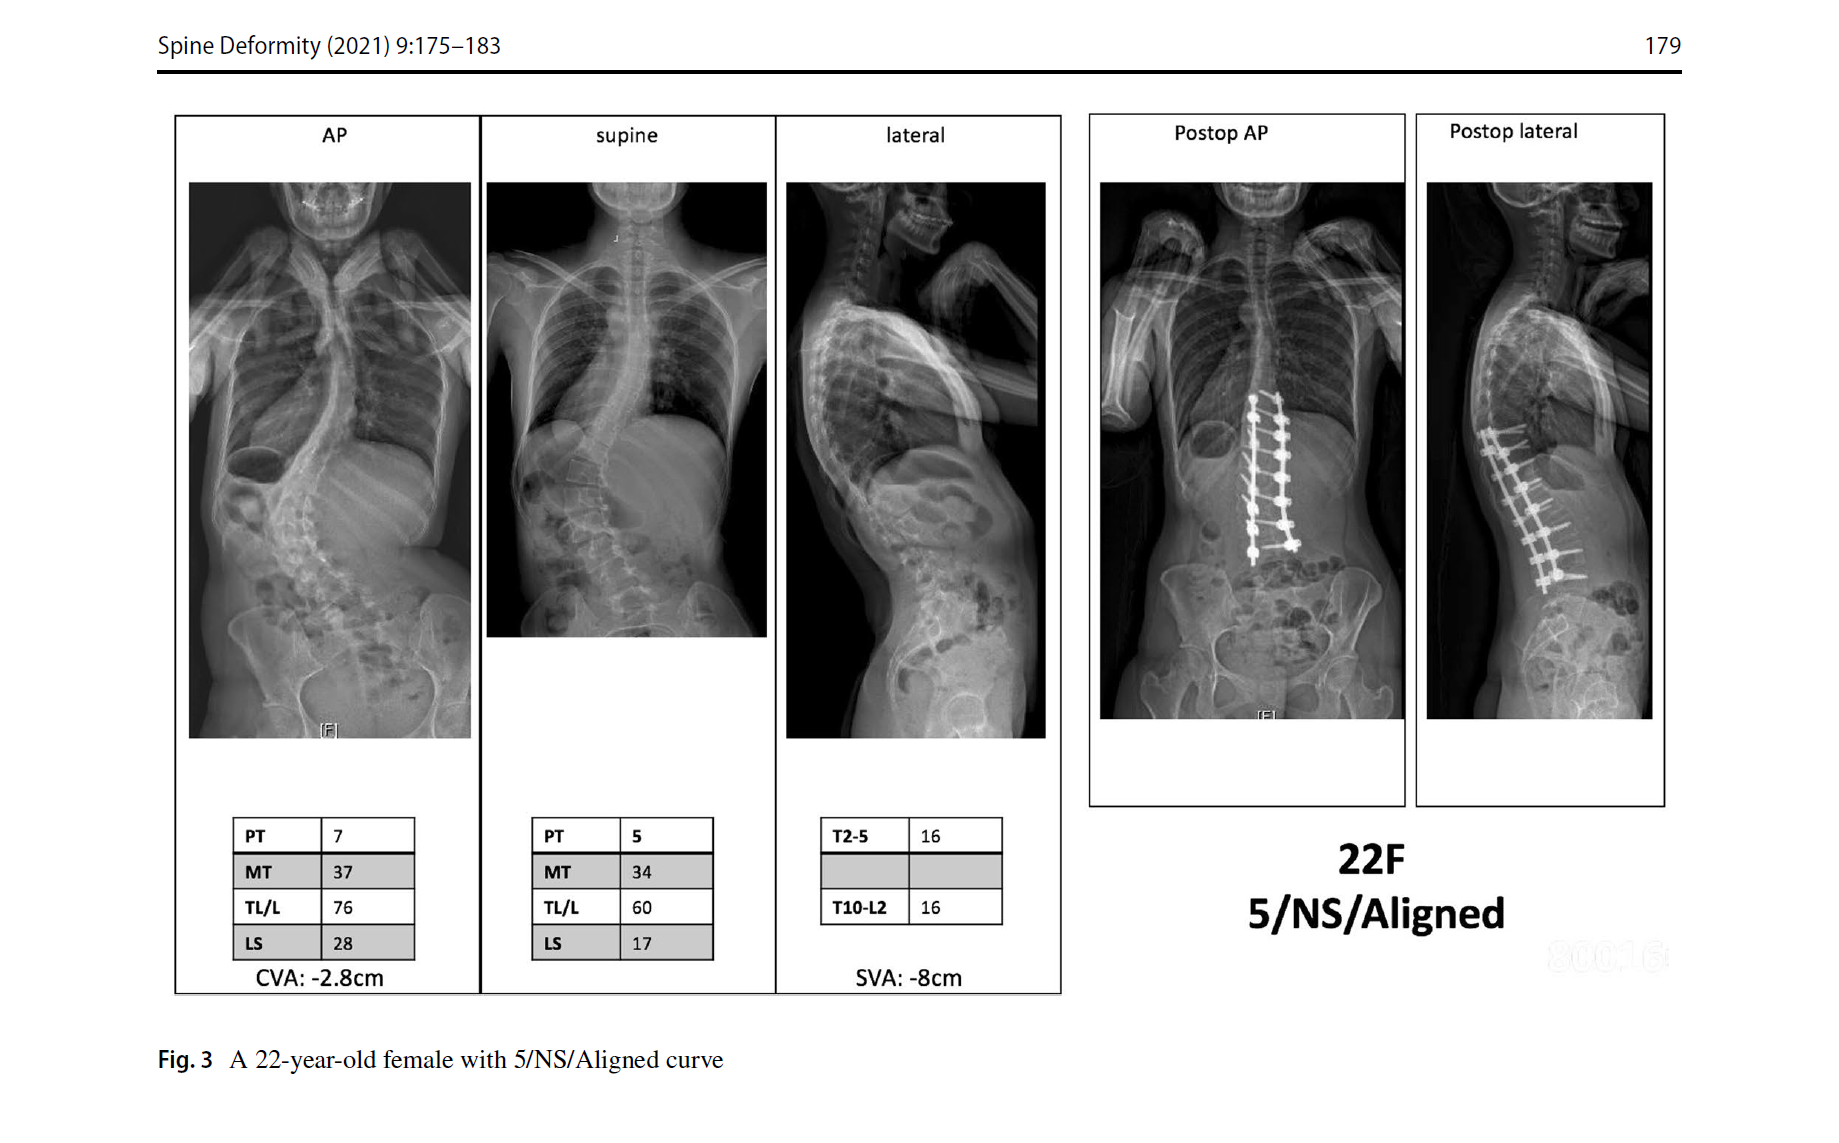

1. 曲线类型分为6型,与Lenke AIS完全一样。但结构弯的标准为:仰卧位全长位Cobb角大于35度,或者后凸大于20度。这与AIS不同,也摒弃了bending位片。

2. 腰骶椎修正,是本分型的特别和关键之处。定义为仰卧位片L4上终板到S1上终板的Cobb角。大于20度为结构弯(S),需要融合腰骶段。小于20度为非结构弯(NS),不需要融合腰骶段。

3. 脊柱平衡修正包括了冠状位、矢状位和冠矢合并的平衡状态。标准与SRS基本一致,冠状位失衡CVA≥40mm,矢状位失衡SVA≥40mm。排列组合,共有Aligned、Sag Malalign、Cor Malalign、or Comb Malalign 4种类型。如果脊柱失衡,需要按SRS标准矫正。

文中的病例片子很漂亮,看图知意,很容易让读者理解这个分型。